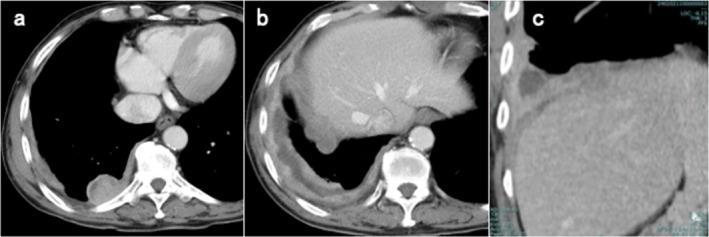

Detailed clinical data on the combination immune checkpoint inhibitor (ICI) therapy in patients with myasthenia gravis (MG) remain limited. We report a case of malignant pleural mesothelioma with previously undiagnosed ocular MG. Owing to hepatic dysfunction, reduced doses of nivolumab and ipilimumab were administered before confirmation of anti-acetylcholine receptor (AChR) antibody positivity. MG was diagnosed based on subtle ocular symptoms and serological tests. Prophylactic intravenous immunoglobulin and an acetylcholinesterase inhibitor were administered; combination therapy was discontinued owing to the risk of MG flare, but a partial tumour response was achieved. With disease progression, nivolumab monotherapy was reintroduced, and early steroid pulse therapy was administered owing to elevated creatine kinase, again inducing a partial response. Serological screening for anti-AChR antibodies may help prevent severe MG flares and immune-related adverse events. With caution, dose-reduced and limited-exposure ICI combination therapy may be feasible in selected patients with MG under appropriate prophylactic management.

重症肌无力(MG)患者联合免疫检查点抑制剂(ICI)治疗的详细临床数据仍然有限。我们报告一例患有先前未诊断出的眼肌型MG的恶性胸膜间皮瘤病例。由于肝功能障碍,在确认抗乙酰胆碱受体(AChR)抗体阳性之前,给予了减量的纳武单抗和伊匹木单抗。基于轻微的眼部症状和血清学检查诊断为MG。给予预防性静脉注射免疫球蛋白和乙酰胆碱酯酶抑制剂;由于MG发作风险,停止联合治疗,但实现了部分肿瘤缓解。随着疾病进展,重新引入纳武单抗单药治疗,由于肌酸激酶升高给予早期类固醇冲击治疗,再次诱导部分缓解。抗AChR抗体的血清学筛查可能有助于预防严重的MG发作和免疫相关不良事件。谨慎地说,在适当的预防性管理下,减量和有限暴露的ICI联合治疗在选定的MG患者中可能是可行的。